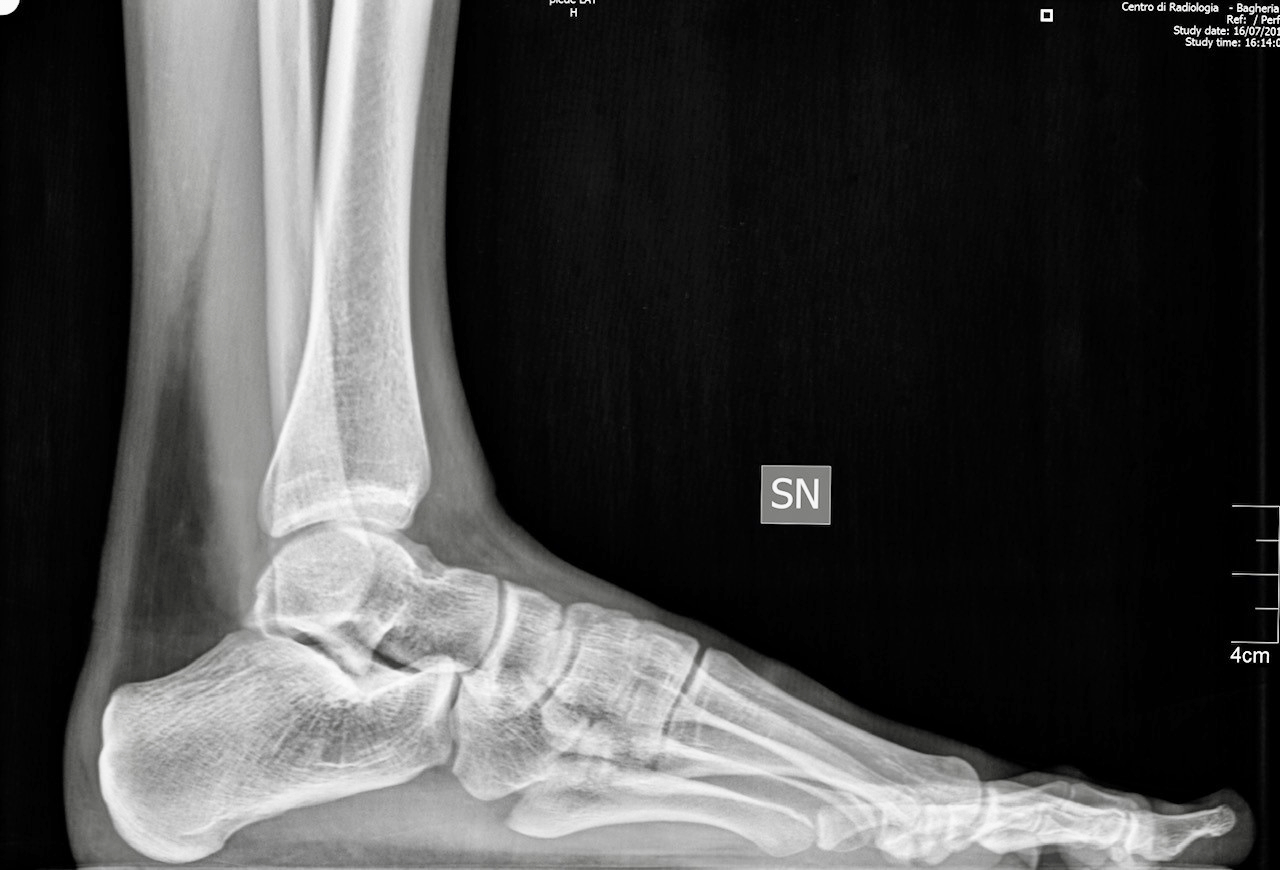

Nel Centro di Radiologia Muglia - Rago - Scaletta si eseguono tutti gli esami di routine dello scheletro, degli organi toraco-addominiali e gli esami contrastografici per lo studio della patologia intestinale ed in particolare la videofluorografia delle vie digestive superiori. La struttura si avvale di apparecchiature moderne e all’avanguardia, che ne fanno un innovativo centro di radiologia digitale a Bagheria e nei comuni limitrofi.

Il centro di radiologia è dotato di un sistema wireless per l'invio immediato delle immagini radiografiche ad un computer, mantenendo una qualità elevata ed evitando superflue esposizioni dei pazienti ai raggi X.

Tutte le immagini acquisite, trattate con un sofisticato post processing, vengono registrate su un supporto digitale (DVD).